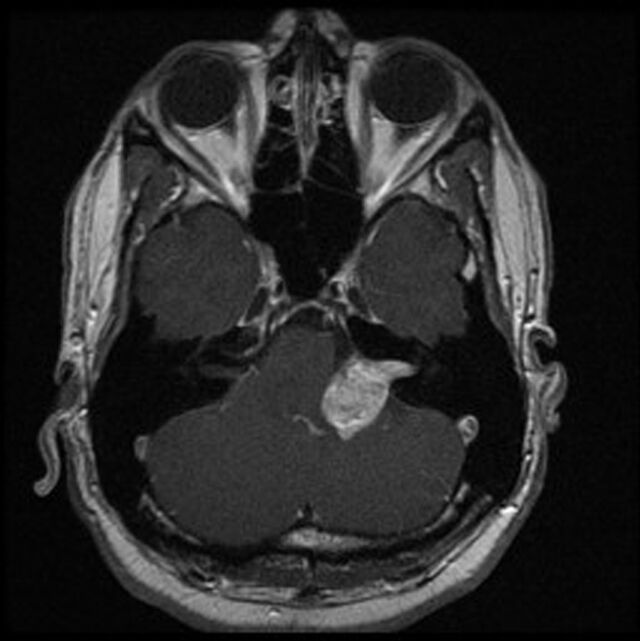

• Das „Akustikusneurinom“ (besser: Vestibularisschwannom, weil es sich fast immer am Gleichgewichtsnerven [Vestibularis] bildet) ist eine gutartige Geschwulst. Sie hat nichts mit Krebs zu tun und bildet keine Tochtergeschwülste (Metastasen).